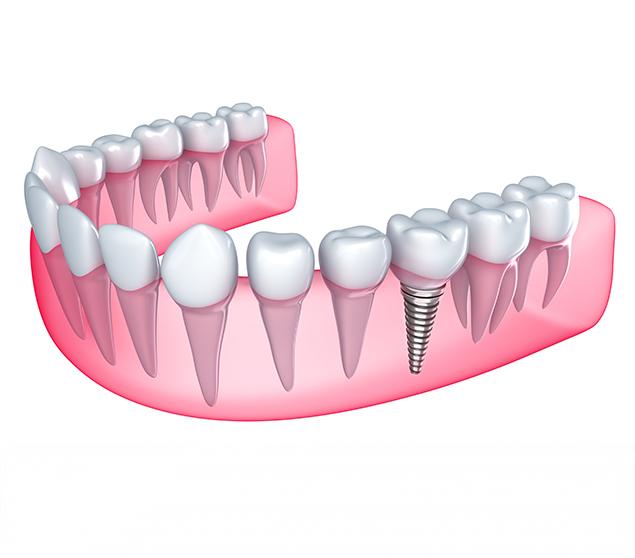

Dental implant treatment involves several steps, including planning, placement, healing, and restoration. The process and timeline vary depending on individual factors such as bone health and the number of teeth involved.

Our team explains each stage in advance so you know what to expect and can make informed decisions about your care.